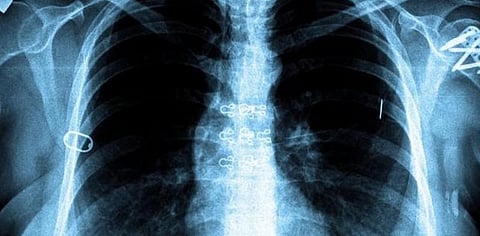

தமிழ்நாட்டில் அதிகரிக்கும் காசநோய் பாதிப்பு - ஆய்வறிக்கை

தமிழகத்தில் கடந்தாண்டில் மட்டும் புதிதாக 1.03 லட்சம் பேர் காச நோயால் பாதிக்கப்பட்டிருப்பது கண்டறியப்பட்டுள்ளது.

மத்திய சுகாதார மற்றும் குடும்ப நல அமைச்சகம் வெளியிட்டுள்ள அறிக்கையில், கடந்த 2018-ஆம் ஆண்டு ஜனவரி 1 முதல் டிசம்பர் 31-ஆம் தேதி வரையிலான காலகட்டத்தில் நாட்டில் 21.32 லட்சம் பேர் புதிதாக காசநோயால் பாதிக்கப்பட்டிருப்பது கண்டறியப்பட்டுள்ளது. இதில் உத்தரப்பிரதேச மாநிலத்தில் அதிகப்பட்சமாக 4.10 லட்சம் பேர் காசநோயால் பாதிக்கப்பட்டுள்ளனர். இந்த வரிசையில் தமிழகம் ஆறாவது இடத்தில் உள்ளது. தமிழகத்தில் கடந்தாண்டில் மட்டும் புதிதாக 1.03 லட்சம் பேர் காச நோயால் பாதிக்கப்பட்டிருப்பது தெரியவந்துள்ளது.

தென்இந்தியாவை பொருத்தவரை தமிழகத்தில் தான் கடந்தாண்டில் அதிகம் பேர் காசநோயால் பாதிக்கப்பட்டிருப்பது தெரியவந்துள்ளது. கடந்த ஆண்டு ஆந்திராவில் 91,157 பேரும், கர்நாடகாவில் 83,732 பேரும், தெலங்கானாவில் 52,395 பேரும் காசநோயால் பாதிக்கப்பட்டிருப்பது தெரியவந்துள்ளது. கேரளாவில் குறைவாக 24,535 பேர் காசநோயால் பாதிக்கப்பட்டிருப்பது கண்டறியப்பட்டுள்ளது. 2025-ஆம் ஆண்டுக்கள் இந்தியாவில் காசநோயால் பாதிக்கப்பட்டவர்களே இல்லை என்ற நிலையை உருவாக்க இந்திய அரசாங்கம் நடவடிக்கை எடுத்து வருவது குறிப்பிடத்தக்கது.